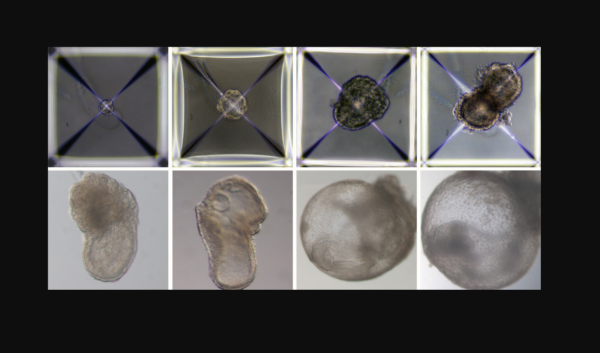

Επιστήμονες δημιούργησαν τα πρώτα «συνθετικά έμβρυα» στον κόσμο

Δομές παρεμφερείς με έμβρυα κατάφεραν να δημιουργήσουν επιστήμονες από το Ισραήλ παρακάμπτοντας το συμβάν της γονιμοποίησης και την ανάγκη κυοφορίας τους σε μήτρα. Οι ερευνητές ελπίζουν ότι η ανακάλυψή τους θα ανοίξει το δρόμο για νέες πηγές κυττάρων και ιστών για μεταμοσχεύσεις